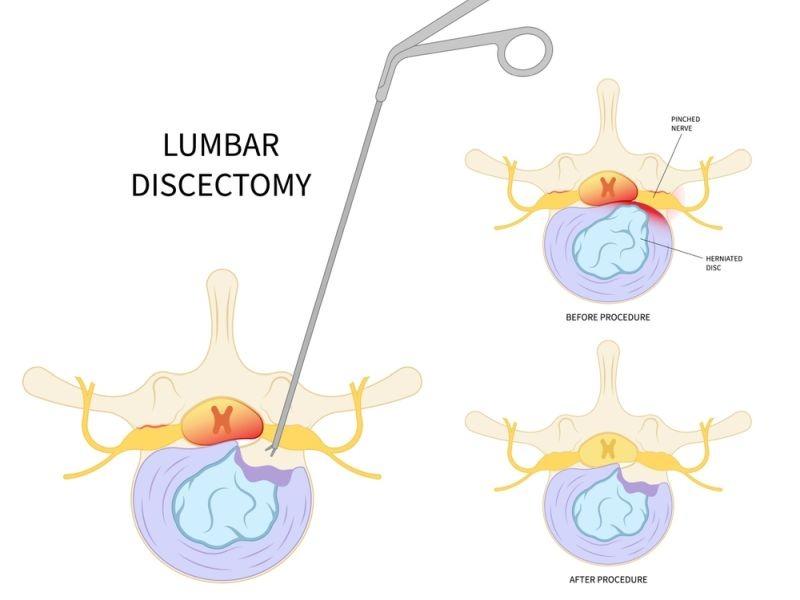

Endoscopic Discectomy in Thane - Targeted Relief for Herniated Disc Pain